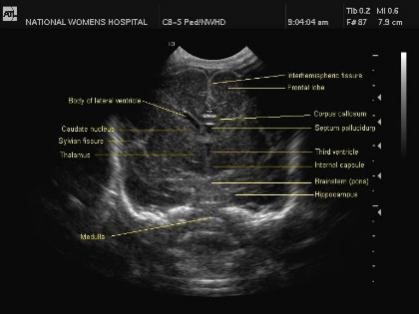

1. Midline Sagittal

The image gives some important information. It shows the cerebellar vermis as a bright image with the 4th ventricle right in front of it. Right below the cerebellar vermis is the cisterna magna, which is not that bright. With the cingulated gyrus right above, the corpus callosum sweeps from anterior to posterior. A bit further above the posterior fossa is the parieto-occipita sulcus.